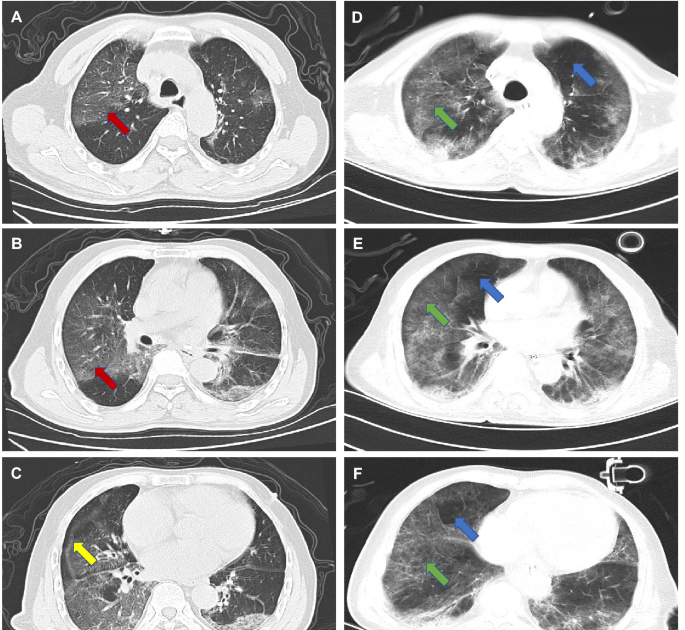

Covid Pneumonia Chest X Ray. Review/update the information highlighted below and resubmit the form. Covid is possibly better diagnosed using radiological imaging fang, 2020.

Covid is possibly better diagnosed using radiological imaging fang, 2020. Review/update the information highlighted below and resubmit the form. This can help your doctor visualize changes in.

Companies are developing ai tools and deploying them at hospitals wired 2020. Covid is possibly better diagnosed using radiological imaging fang, 2020. When viewed against a lit background, your doctor can look.